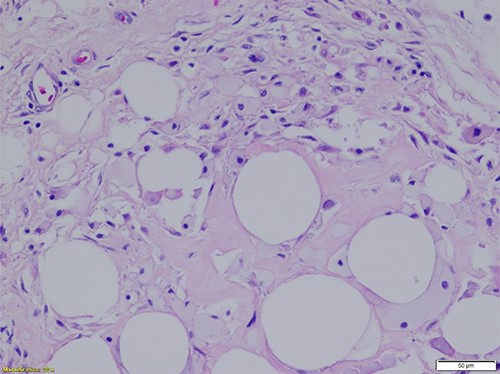

Histopathologic evaluation of representative hematoxylin and eosin (H&E)-stained sections from each specimen were similar and showed mature adipocytes of typically uniform size with foci of degeneration of fat necrosis. Adipocytes did show varying sizes in these regions of necrosis and degeneration. The tumors exhibited the typical fibrous septal vascularity of mature, benign lipomas. Rarely, focal microcalcifications are seen in areas of fat necrosis with degenerative adipocyte changes (Figs 1 and 2).

Mature adipocytes of a benign lipoma with relatively scant, septal vascularity and foci of fat necrosis (H&E-stained section; ×40 total magnification: ×4 objective with ×10 ocular lens) (Courtesy Karl Biesemier, MD. Pathology Consultants of Central Virginia, Lynchburg, VA).